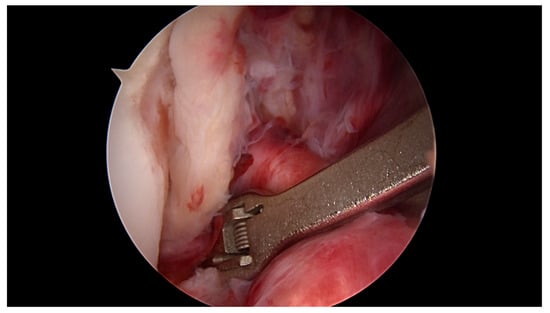

All surgeries were performed under spinal anaesthesia with the affected leg placed in an adjustable leg holder and with administration of an intravenous antibiotic prophylaxis. An examination under anaesthesia of the knee was performed prior to surgery in order to confirm ACL instability. The standard anterolateral and anteromedial portals were established to perform the arthroscopy to confirm all suspected findings with a probe. The ACL was assessed regarding tear pattern and tissue quality. When a proximal tear pattern with good tissue quality was identified (Figure 2), the patient was deemed eligible for arthroscopic ACL repair using SA: a labral scorpion suture passer (Arthrex, Naples, FL, USA) was used to pass a No. 2 FiberWire® (Arthrex, Naples, FL, USA) 3 times approximately 1 cm distal to the tear through the ACL remnant (Figure 3 and Figure 4). The femoral tunnel was drilled in anatomic manner within the footprint with 130 degrees knee flexion using a spade tip drill pin (Arthrex, Naples, FL, USA). An arthroscopic 45 degrees awl was used to perform a microfracture near the femoral footprint to enhance healing (Figure 5). Afterwards, a shuttling loop was passed through the femoral tunnel. The tibial drilling guide (Smith and Nephew, Andover, MA, USA) was placed at the anterior centre of the tibial footprint and a small skin incision at the anteromedial aspect of the proximal tibia was established to allow drilling and shuttling of a loop through the tibial tunnel. The tibial and femoral shuttling loop as well as the FiberWire® suture were retrieved through the anteromedial portal, the latter two placed in the tibial shuttling loop and passed through the tibial tunnel. Using the femoral shuttling loop, the SA construct containing a FiberTape® (Arthrex, Naples, FL, USA) armed TightRope® (Arthrex, Naples, FL, USA) and the FiberWire® were carefully shuttled through tibia and femur so that the TightRope® button flipped at the femoral cortex. The FiberTape® was fixed distally at the anteromedial tibia with a 4.75 SwiveLock® (Arthrex, Naples, FL, USA) with the knee in full extension. Subsequently, the FiberWire® suture and TightRope® tensioning suture were knotted on tension completing the ACL repair (Figure 6). Concomitant meniscal injuries were addressed either with direct repair (RapidLoc®, Mitek Products, Westwood, MA, USA) or with cautious partial resection when repair was deemed not feasible due to the configuration of the tear or pre-existing degenerative meniscopathy (Table 1). Concomitant chondral injuries were carefully smoothed or prudently underwent nano-fracture under direct vision.

Figure 5. An arthroscopic 45 degree awl is used to perform focused microfracture near the femoral.